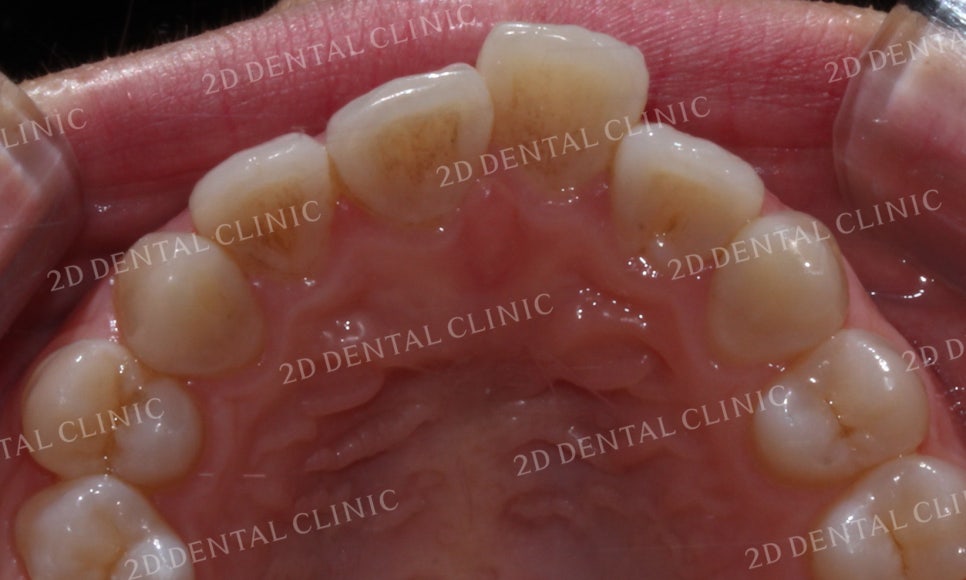

전치부 사진을 보시면

중절치(21번)가 다른 치아들보다

확실히 돌출된 모습입니다.

이러한 덧니의 경우 치열이 고르지 못하고

삐뚤거리기 때문에 치석과 플라그가 쉽게 쌓일 수 있습니다.

따라서 치아 사이에 잔여 음식물이 남지 않도록

교정기간 중에도 꼼꼼한 관리가 필요합니다.

상악의 안쪽면 사진에서도

중절치의 덧니 증상을 확인할 수 있습니다.